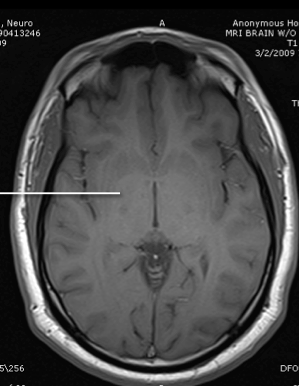

lateral ventricle

posterior horn of the internal capsule

thalamus

anterior limb of the itnernal cpasule